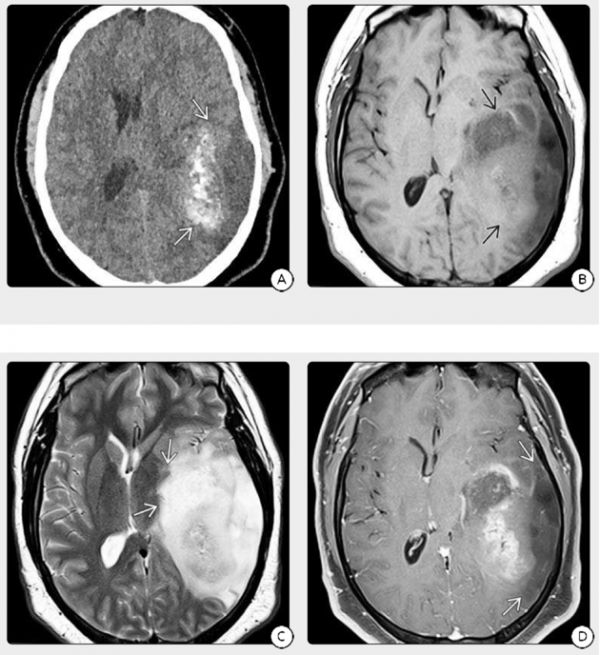

IDH突變型GBM原發(fā)部位對(duì)額葉有獨(dú)特的(但非排他性)偏愛(ài)。通常存在明顯的非增生區(qū)域,并且通常不存在典型的厚腫瘤外皮,該外皮圍繞著以IDH野生型GBM為特征的大中央壞死核(圖2)。例外情況很常見(jiàn),因此仍然需要進(jìn)行分子譜分析來(lái)確定診斷。MRS可能會(huì)揭示一個(gè)在2.25 ppm處共振的2-HG峰。

圖2:6歲男童,(A)CT示左顳顳頂區(qū)域的一部分鈣化了混合密度質(zhì)量,(B)在相同情況下的MR顯示侵犯灰質(zhì)、白質(zhì)的混合信號(hào)大面積占位,(C)T2WI和FLAIR顯示,腫塊幾乎累及所有顳葉和頂葉,向內(nèi)側(cè)延伸至基底神經(jīng)節(jié)和丘腦,(D)T1 C+FS顯示腫塊具有斑片狀的增強(qiáng)區(qū)域,但大部分腫塊沒(méi)有增強(qiáng)。繼發(fā)性GBM通常存在鈣化和較大的非增強(qiáng)區(qū)域,病理證實(shí)腫瘤是IDH突變的GBM,它起源于較低級(jí)別的星形細(xì)胞瘤。